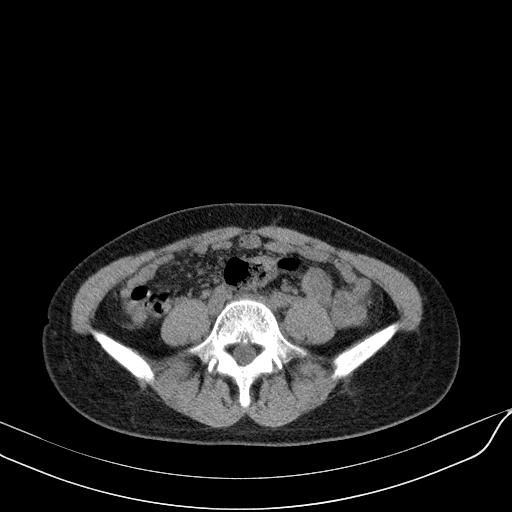

标题: CT23965:无外伤史,下腹痛 [打印本页]

标题: CT23965:无外伤史,下腹痛

肠道未准备,继续往下扫,乙状结肠占位不排除。建议钡灌或结肠镜检查。

乙状结肠占位不排除

未见明显异常改变,做个气钡双重造影除外一下结肠病变,无外伤史为啥不常规喝泛影葡胺水对比剂再扫ct呢?

肠道肿瘤,建议行钡剂灌肠检查。